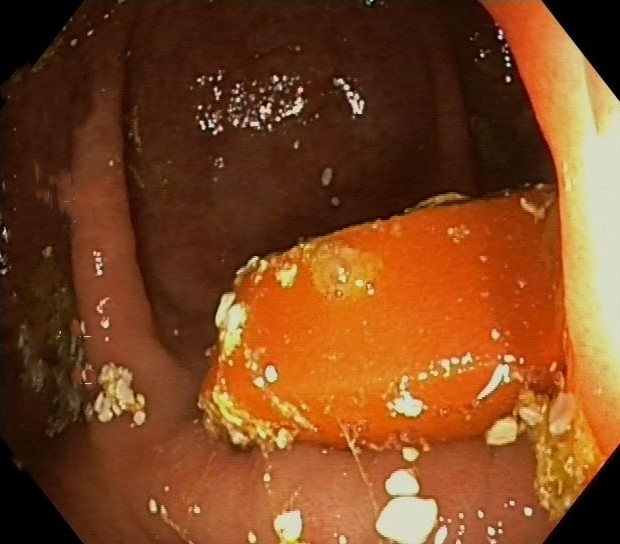

Asacol Tablets in the Caecum, Inactive Ulcerative Colitis

Asacol Tablets in the Caecum, Inactive Ulcerative Colitis. Just click on a picture!